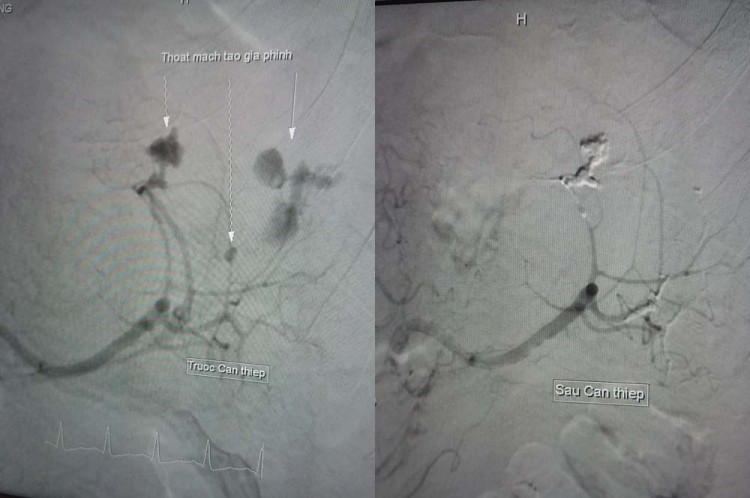

Hình ảnh trước qua sau khi can thiệp cho bệnh nhân

Tại đây, bác sĩ bơm thuốc cản quang để xác định vị trí động mạch lách bị vỡ. Sau đó, tiếp tục luồn một ống siêu nhỏ vào động mạch đang chảy máu và bơm keo vá chỗ thủng, giúp cầm máu và gắn liền nhu mô lách.